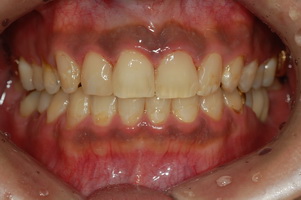

| ÃæÄ¡Ä¡·á¿Í Ä¡¾Æ¼ºÇü |